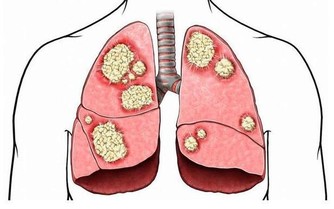

答:氯氣對人體有嚴重危害,它能刺激眼、鼻、喉以及上呼吸道等。引起急性肺水腫及肺炎,濃度高時可麻痹呼吸中樞、出現「閃擊性死亡」。長期吸入低濃度的氯會引起慢性中毒,導致體內產生大量的自由基,加速人體衰老速度。主要病癥為鼻炎、慢性支氣管炎、肺氣腫、肝硬化、動脈粥樣硬化,甚至是癌癥。

答:心臟疾病、冠狀動脈粥樣硬化、貧血癥、膀胱癌、肝癌、直腸癌、高血壓和過敏等癥狀。

答:可導致動脈粥樣硬化、心力衰竭、動脈硬化、心臟病、膀胱癌、肝癌、直腸癌、高血壓。